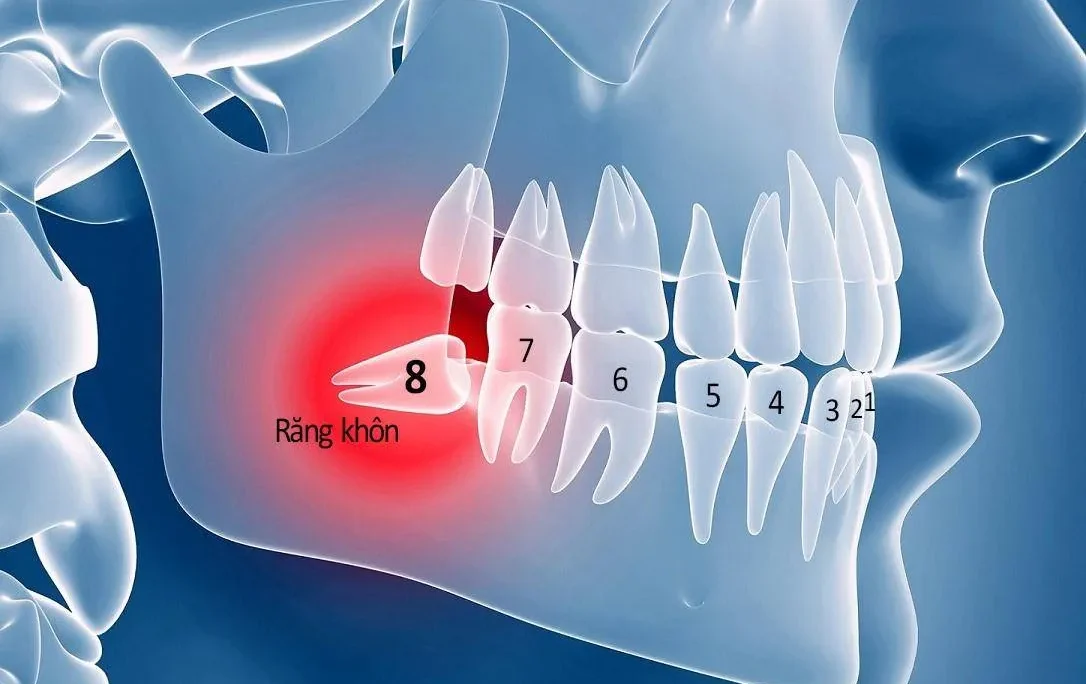

Trong giai đoạn đầu, viêm quanh răng thường bắt nguồn từ mảng bám và cao răng tích tụ lâu ngày, gây kích thích và viêm nhiễm tại các tổ chức liên quan. Bệnh lý này bắt đầu bằng viêm lợi, sau đó lan rộng ra các dây chằng quanh răng và xương ổ răng, làm suy yếu cấu trúc nâng đỡ của răng.

Khi bệnh tiến triển, các mô liên kết bị phá hủy, dẫn đến tụt lợi, răng dễ lung lay hoặc thậm chí mất răng. Điều đáng lo ngại là quá trình này diễn ra âm thầm, ít có triệu chứng rõ ràng ban đầu, khiến nhiều người chủ quan bỏ qua việc chăm sóc cần thiết.